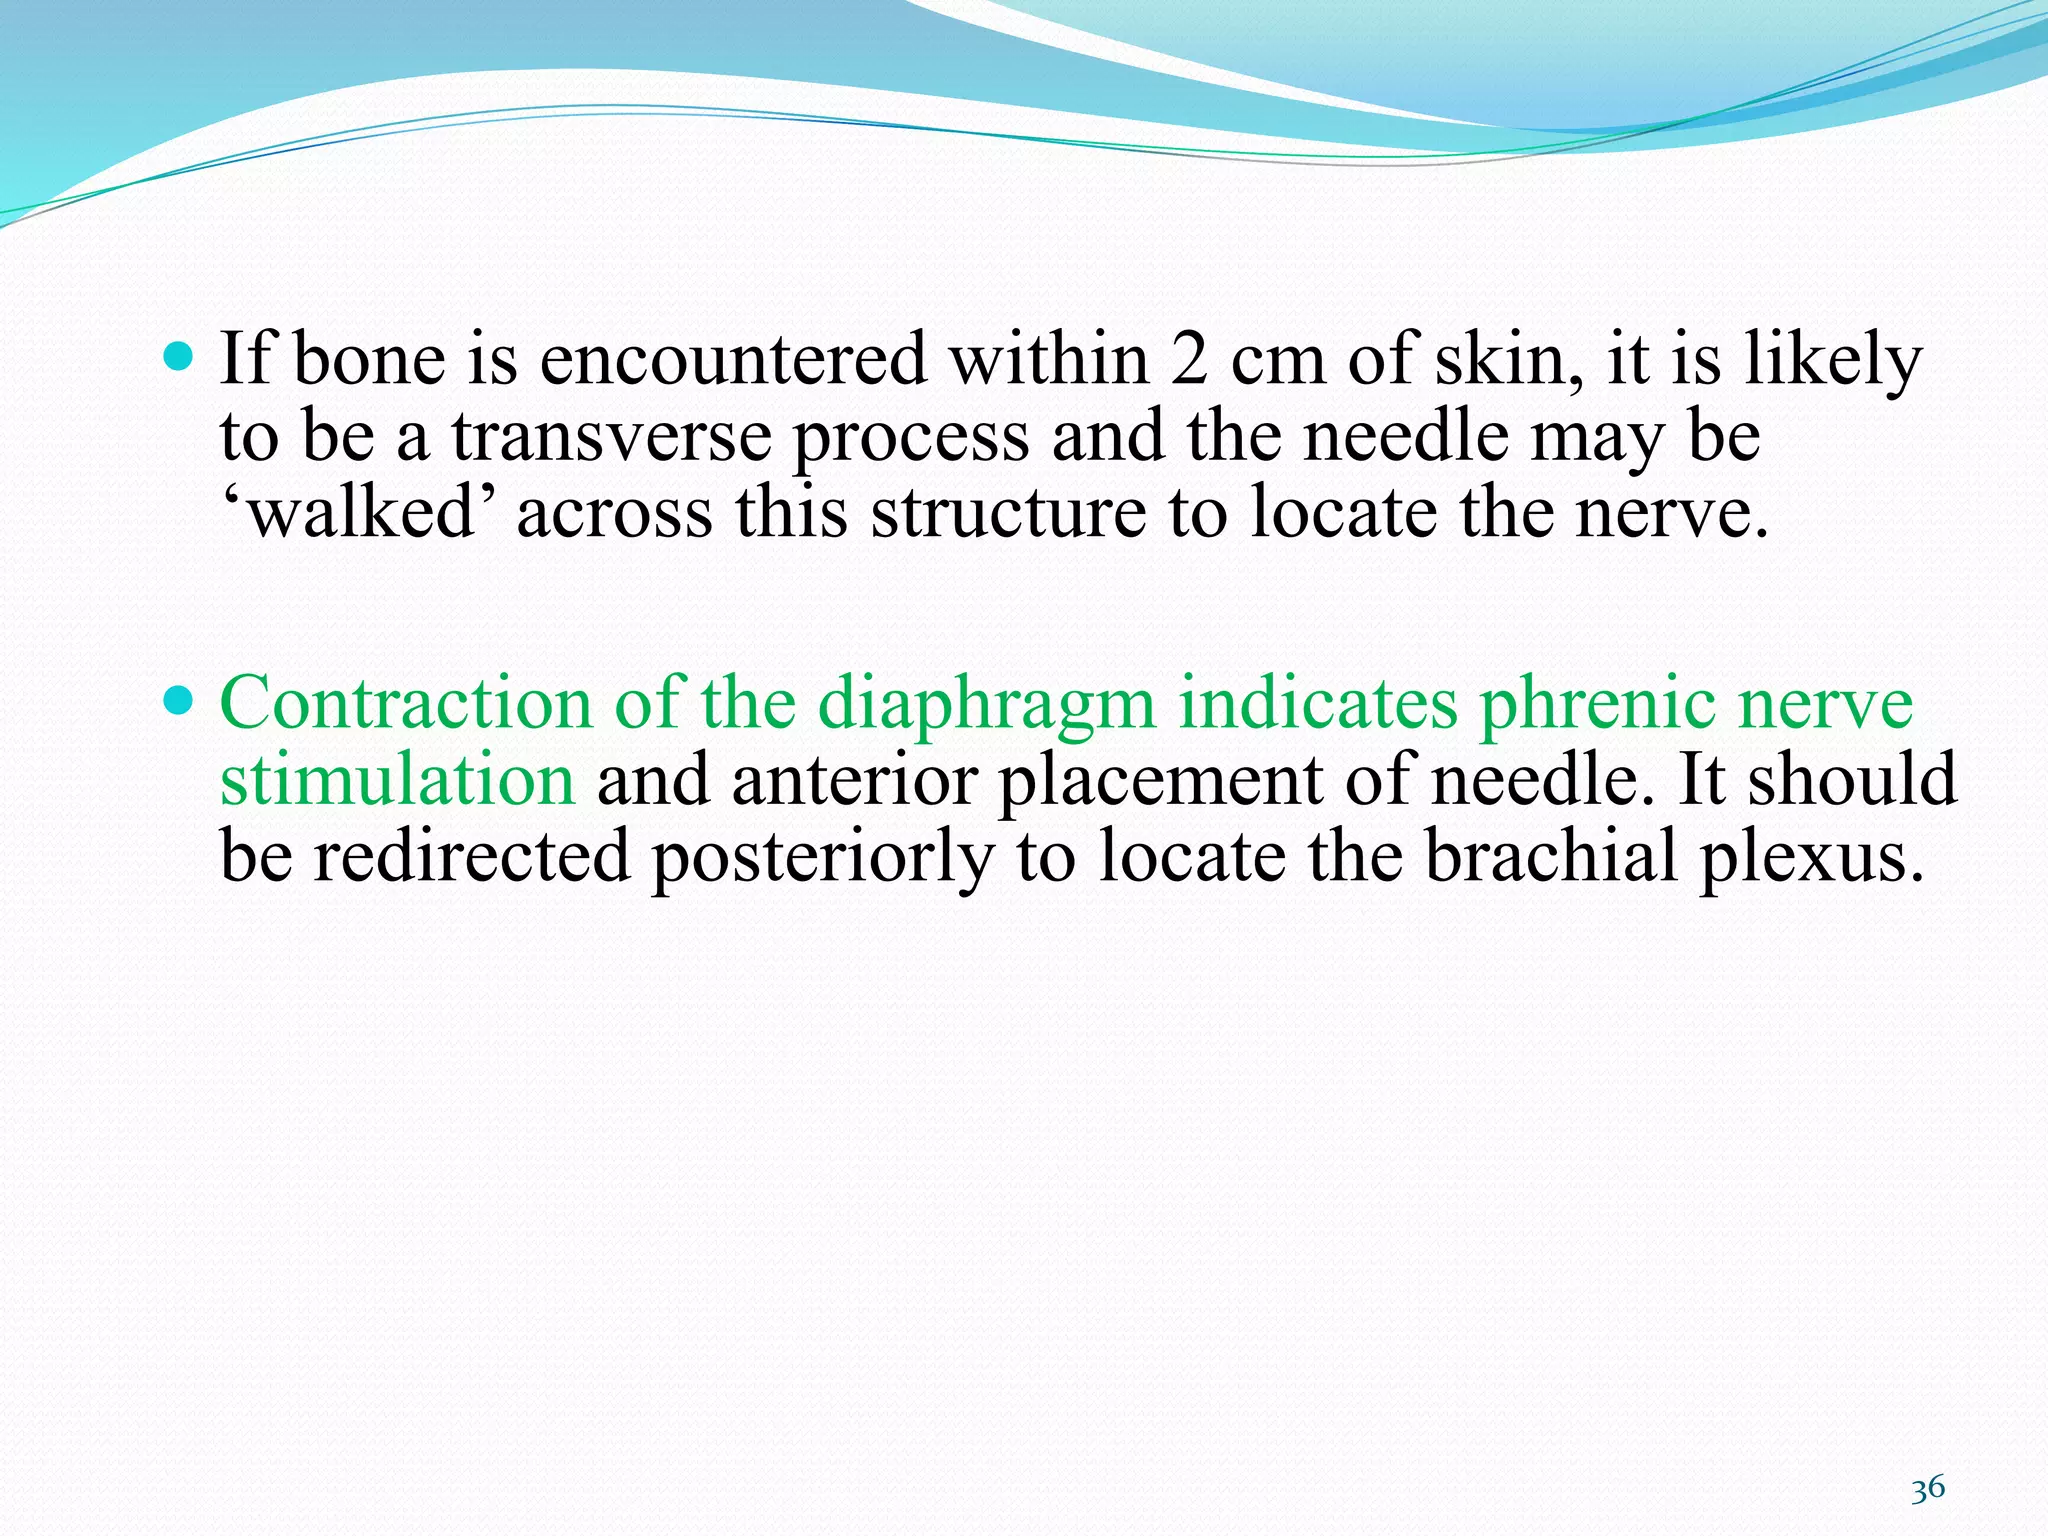

This document provides an overview of brachial plexus anatomy and techniques for brachial plexus nerve blocks. It begins with a description of the brachial plexus formation from cervical and thoracic nerve roots and its branching pattern. Four main approaches for brachial plexus nerve blocks are described: interscalene, supraclavicular, infraclavicular, and axillary. Details are provided on the anatomy and techniques for performing interscalene and supraclavicular brachial plexus blocks. Ultrasound guidance is discussed as an advancement which allows real-time visualization of needle and nerve. Complications are also summarized.